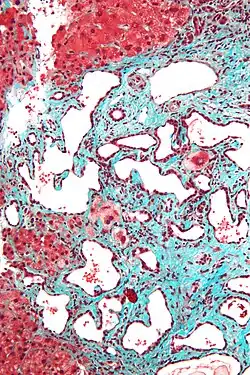

Low magnification micrograph of a bile duct hamartoma. Trichrome stain. -